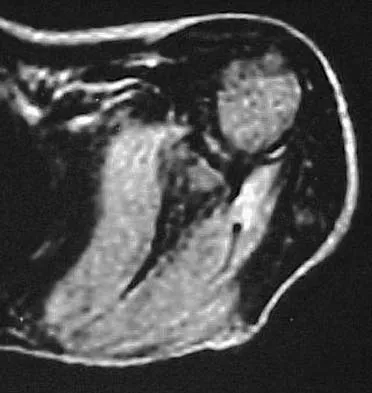

A 13-year-old boy has pain and a firm mass in his left knee. A radiograph and MRI scan are shown in Figures 2a and 2b, and a biopsy specimen is shown in Figure 2c. Based on these findings, what is the most likely diagnosis?

The most likely diagnosis is osteosarcoma. The imaging studies show an aggressive primary tumor of bone, and the histology slide shows a typical chondroblastic osteosarcoma, with osteoid deposited along the surface of bone trabeculae. Ewing's sarcoma histologically consists of small round blue cells. Osteochondroma and periosteal chondroma can occur near the knee but have different radiographic and histologic patterns. Chondrosarcoma rarely occurs in children. Simon M, Springfield D, et al: Osteogenic sarcoma: Surgery for Bone and Soft Tissue Tumors. Philadelphia, PA, Lippincott Raven, 1998, p 267.